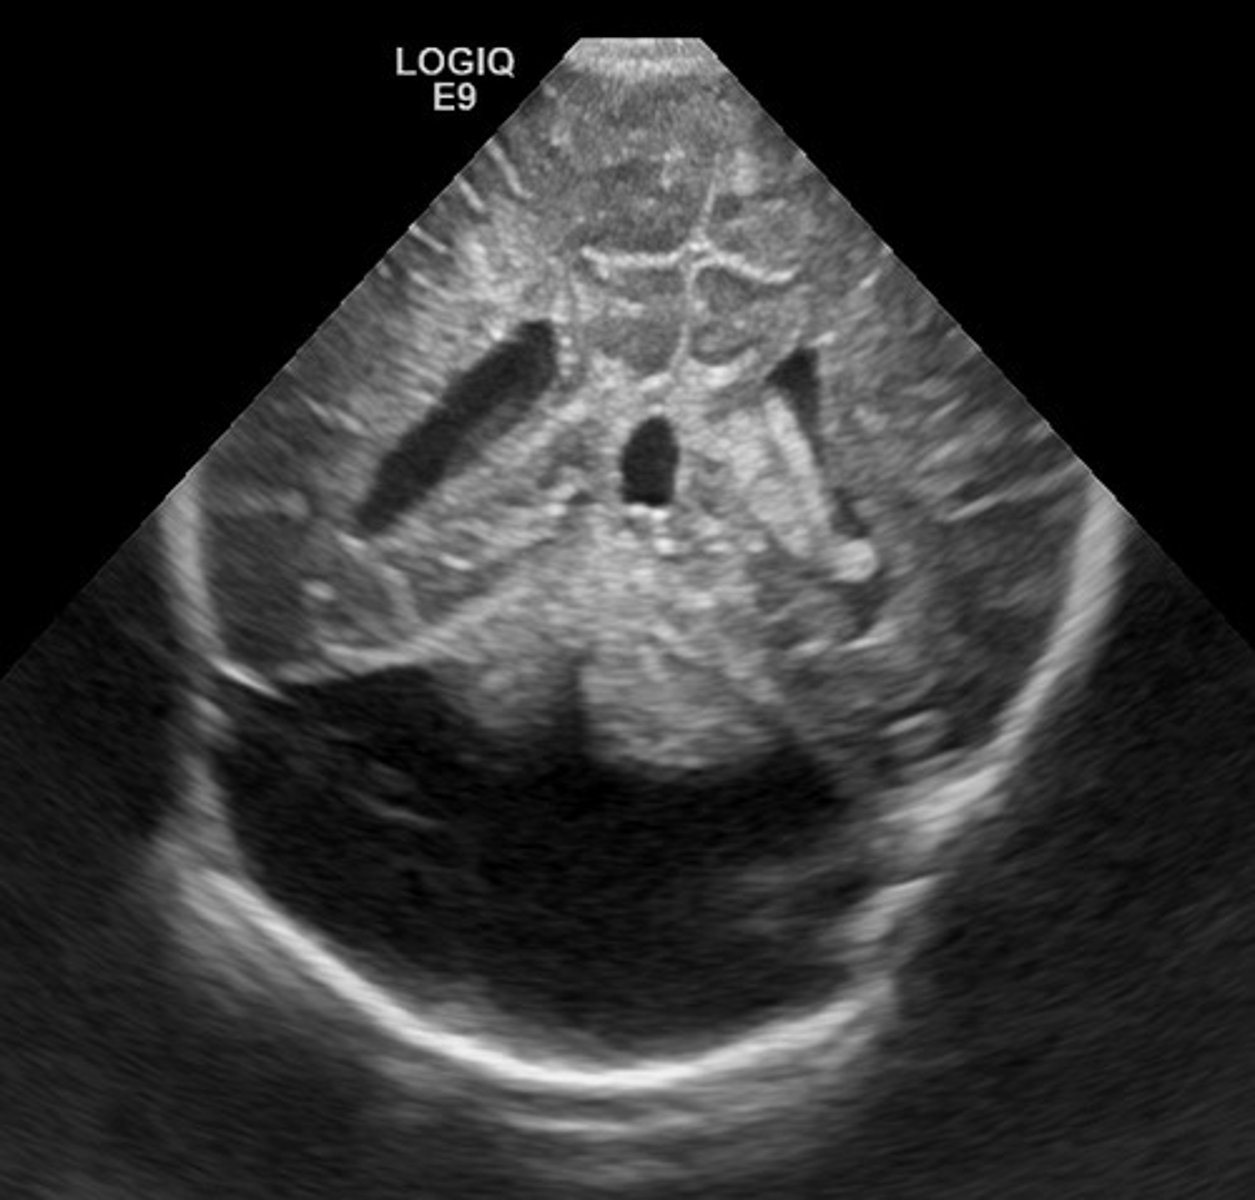

Posterior Urethral Valve Obstruction

Only in boys

Causes bilateral hydronephrosis

Thick bladder walls

Keyhole bladder appearance